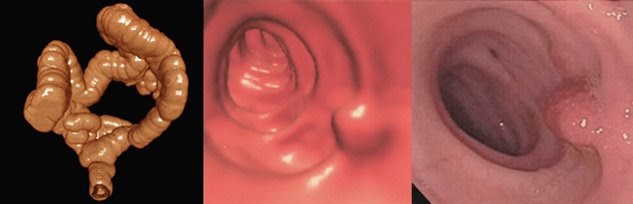

The bill was introduced in the u.s. Getting right to it, yes, medicare pays for colonoscopies. A virtual colonoscopy uses a ct scanner to image the colon and rectum from outside the body.14 medicare does not cover virtual colonoscopies, based on a review of available evidence.15.

What is meals on wheels Medicare may not fully cover these examinations. A virtual colonoscopy (ct colonoscopy) uses a computer rather than a camera to scan the large intestine.

A virtual colonoscopy uses a ct scanner to image the colon and rectum from outside the body. Does medicare cover a 3d mammogram 2021? The information in this article contains billing, coding or other guidelines that complement the local coverage determination (lcd) for virtual colonoscopy (ct colonography) l33452.

Ct, or “virtual”, colonoscopy is an emerging imaging test designed to screen for colon cancer. Part b pays for colonoscopy coverage for screening services like colorectal cancer testing. Coverage includes a broad range of preventive care services, including screenings.